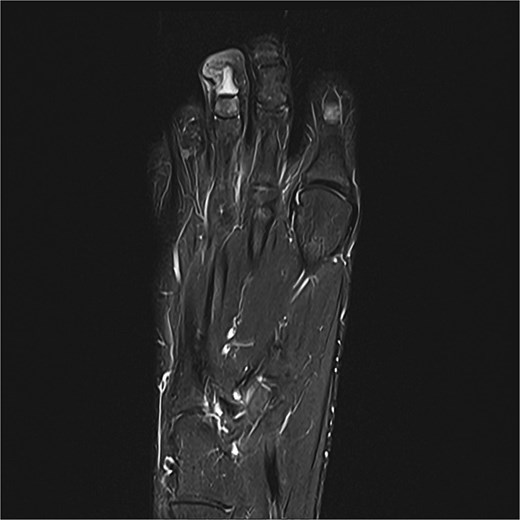

A 14-year-old female presented with recurrent SE of the right great toe (Fig. 4). She had a history of osteomyelitis in the same location, treated successfully before SE developed. MRI confirmed recurrence with underlying osteomyelitis (Fig. 6). Surgery was performed 2 days later (Fig. 5). Bone cultures revealed Staphylococcus sciuri, Staphylococcus caprae, and Staphylococcus warneri, with sparse growth in all five samples. She transitioned to oral dicloxacillin after 1 week of intravenous therapy. At 16 days, she was asymptomatic, and a 3-month follow-up was scheduled.

Preoperative MRI from case 2 demonstrating SE and associated bone marrow edema.